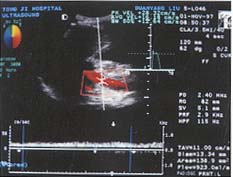

仪器与方法 仪器选用Diasonics Gate-Way ⅡD型电脑彩色多普勒诊断仪,超宽频凸阵探头,频率范围3.5~5MHz,所得资料经仪器光盘存储并录像。所有患者均前晚8时至第二天上午检查前禁食,取仰卧位,通过不同适当断面检测肝内病变的二维及血流信号后,放大显示肝总动脉(CHA)纵轴,将取样点尽量放在靠近肝总动脉的起始处(距起始点1.5cm以内),并测其内径,多普勒取样容积调至稍小于管腔(约为管腔的2/3),取样角度控制在60°以下,摒气获得满意频谱后,测时间平均速度(TAV),由仪器自动测出CHA的血流量,然后自动或手动测定PS、ED、RI。门静脉测量取肝门部门脉主干,均于呼吸末屏气后测量,具体方法同CHA。肠系膜上动脉(SMA)测量取样点位于距起始部约2cm处,方法同CHA。全部测量重复三次以上取平均值,所测频谱为显示好且至少显示三个以上心动周期(见图1~3)。

图2 在距肝总动脉起始部1.5cm范围内测定其各项血流参数

图3 在肠系膜上动脉距起始部约2.0cm处测定各项血流参数